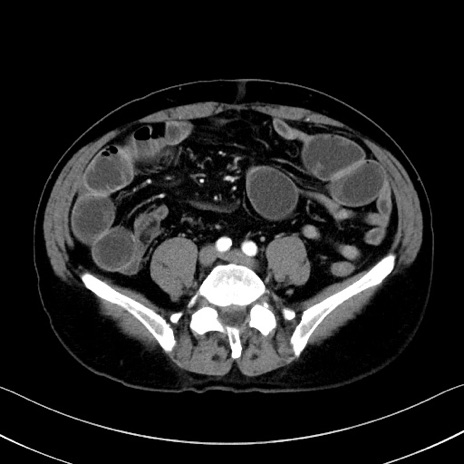

症例35(横断像)

【症例】70歳代 男性

【主訴】腹部膨満、嘔吐

【現病歴】昨日より腹部膨満感出現。本日増悪し、仙痛出現。嘔吐あり、受診。

【既往歴】糖尿病、胆摘後

【身体所見】BP 149/80mmHg、HR 74/min、BT 35.9℃、腹部:膨満、軟、圧痛なし。腸雑音減弱あり。上腹部正中切開瘢痕あり。

【データ】WBC 13500、CRP 1.72